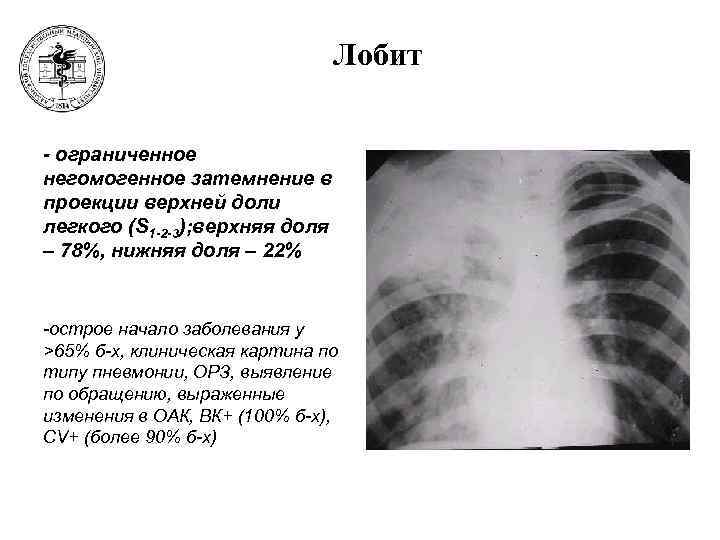

Симптомы и лечение инфильтративного туберкулеза легких

Раздел: Снимки-откровения